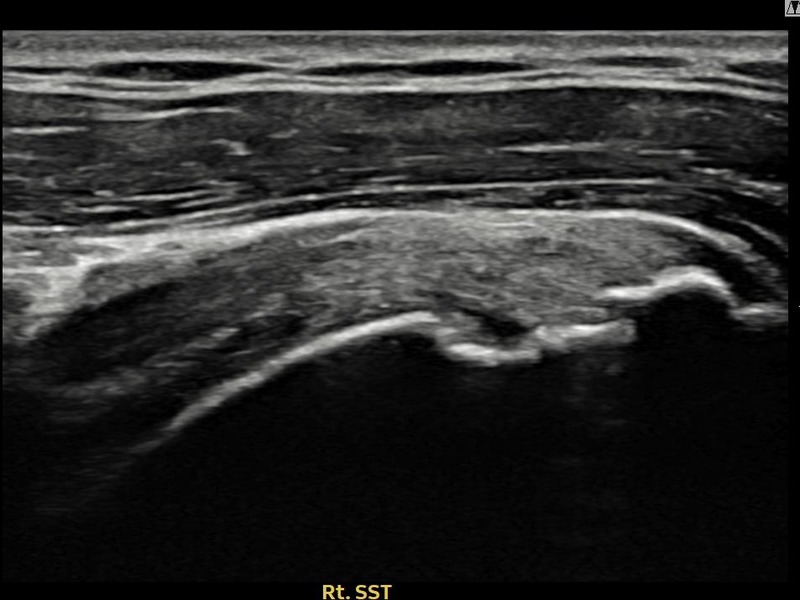

김ㅇㅇ님 · 우측 극상근건 점액낭면측 부분파열

우측 어깨 통증으로 팔을 들어올리기 어렵고 취침 시 통증이 심해 내원하셨습니다. 점액낭면측 부분파열에 대해 축소봉합술을 시행하였고 힘줄 구조가 완전히 회복되었습니다.

상세 보기 →